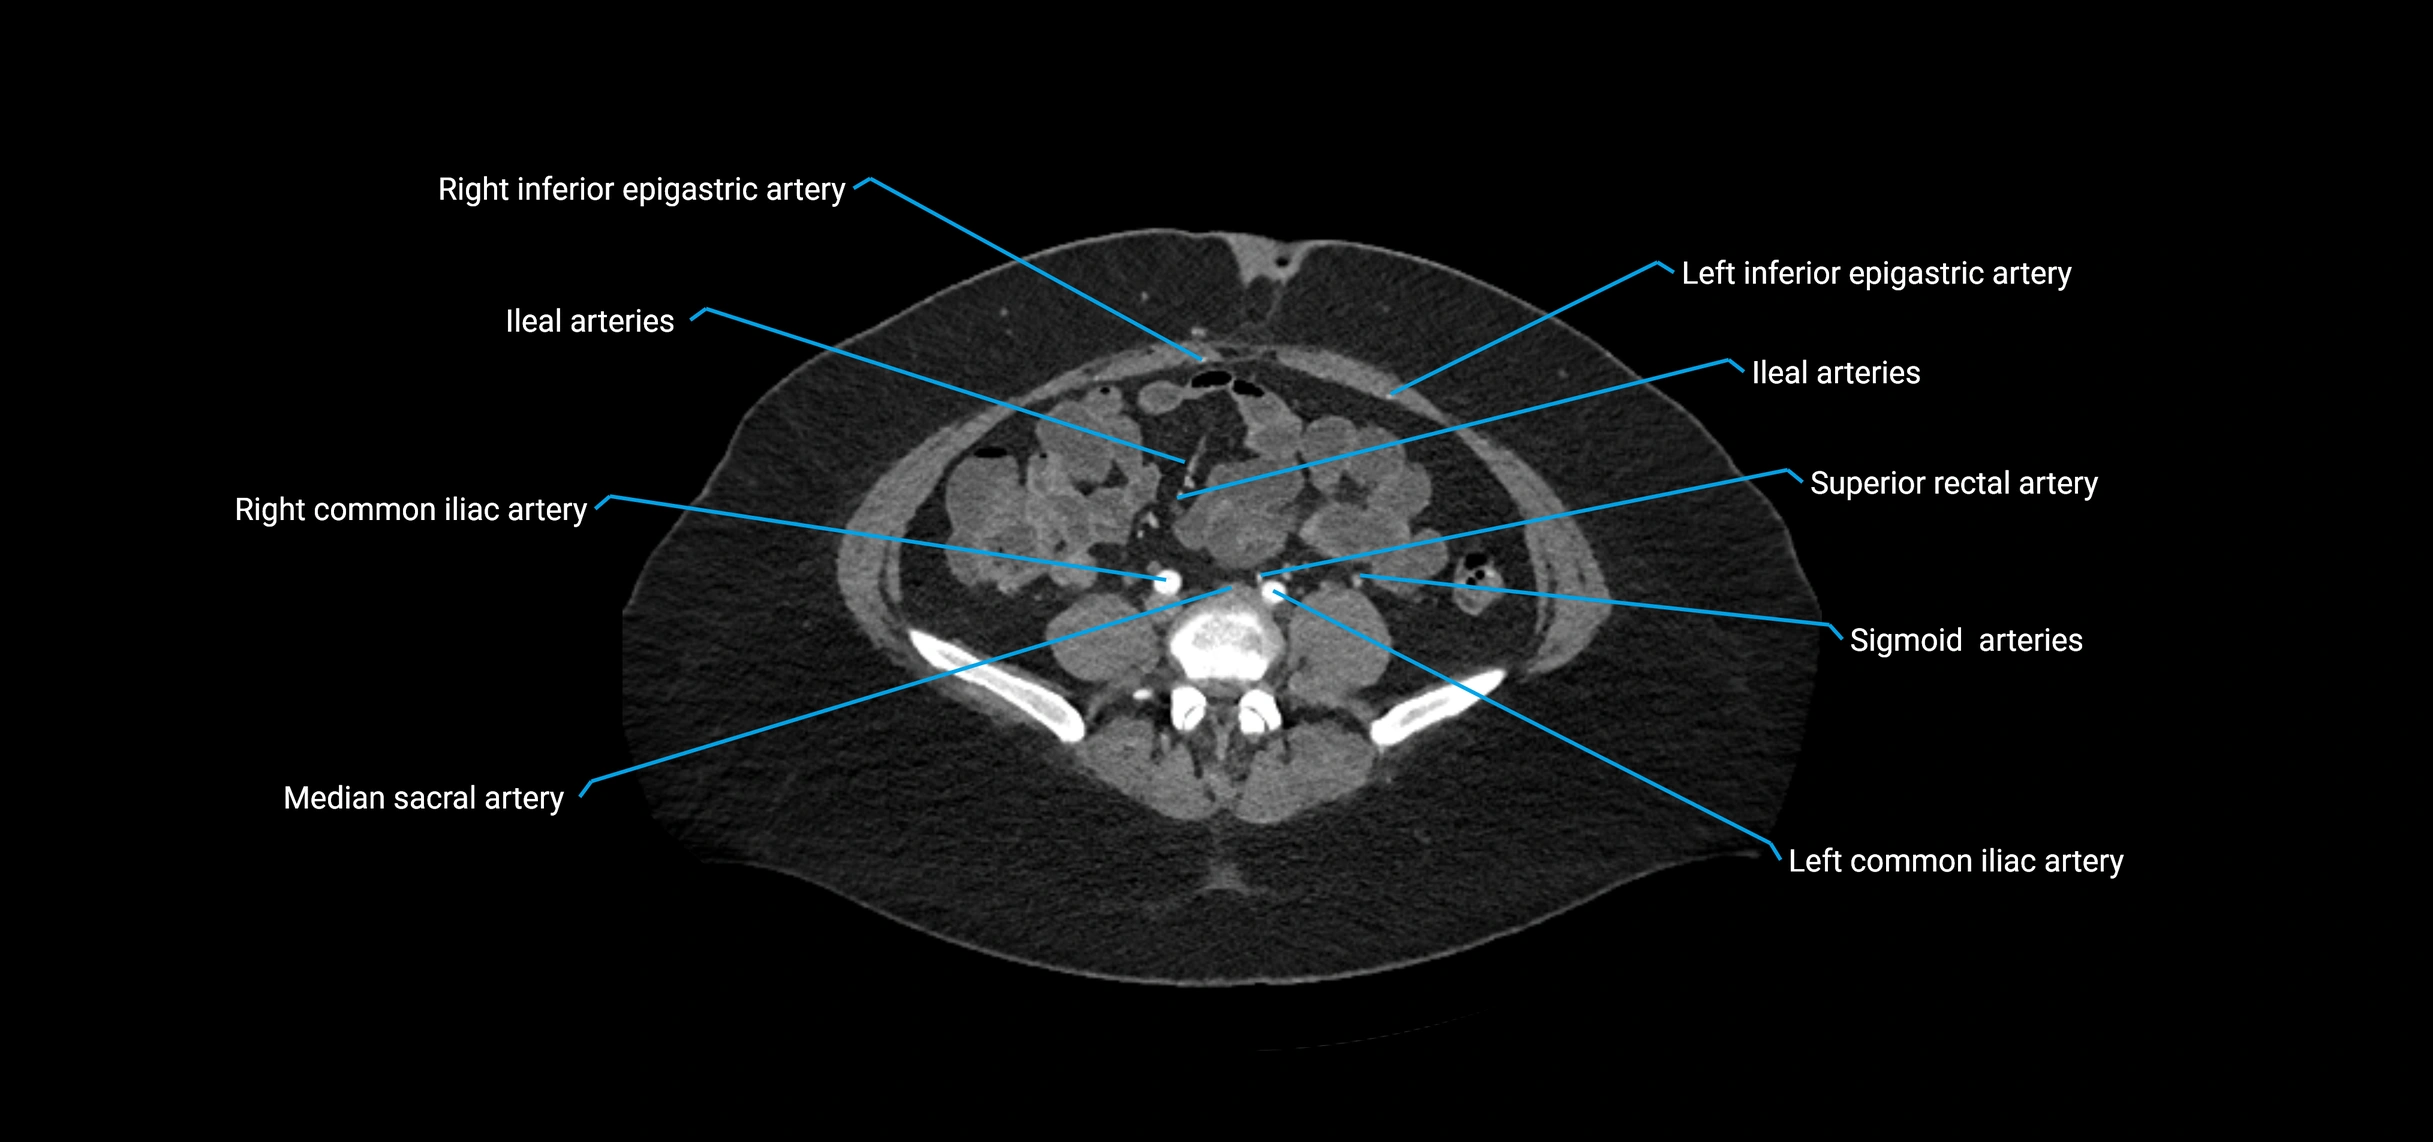

Contrast-enhanced CT (CTA):

• Gold standard for abdominal aortic imaging

• Provides excellent detail of lumen, wall, aneurysm, thrombus, and branch vessels

• Multiplanar and 3D reconstructions help in aneurysm measurement, stent graft planning, and dissection evaluation